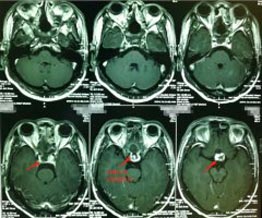

56岁的张先生,3天前出现间歇性头晕,伴有夜间尿多,当地医院就诊,头颅CT检查发现有颅内占位。广东三九脑科医院头颅MRI示:鞍区巨大垂体腺瘤伴瘤卒中,大小约4.3cm×3.1cm×2.8cm,邻近双侧颈内动脉及双侧大脑前动脉受压移位,右侧颈内动脉部分被包绕,视交叉明显受压上抬并向前移位。头颅CTA示大脑前交通囊状动脉瘤,大小约4.6mm×3.4mm。

▲术前MR ▲术前DSA